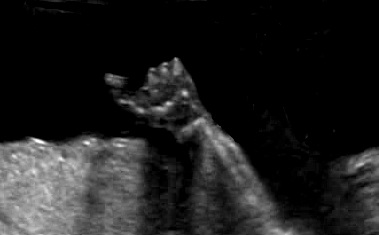

2) labioschisi con o senza palatoschisi;